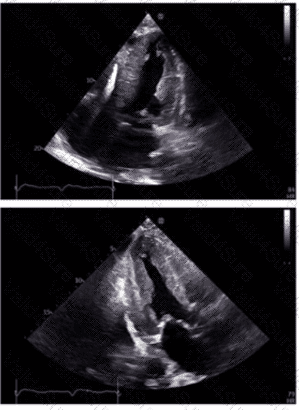

Which echogenic structure is indicated by the arrow on this image?

A.

Vegetation

B.

Tumor

C.

Thrombus

D.

Annular calcification